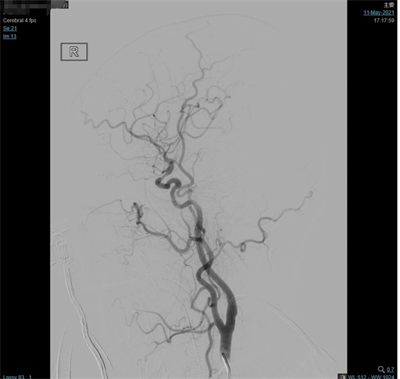

夹闭前造影

夹闭后造影

患者气管插管全麻满意后,双侧腹股沟区常规消毒铺巾,右侧腹股沟韧带下方股动脉搏动最强点下方约1.5cm处穿刺,右股动脉行Seldinger穿刺,置入5F动脉鞘,超滑泥鳅导丝携带5F单弯造影管分别行双侧颈总动脉、双侧颈外动脉及双侧椎动脉正侧位造影,造影见:右侧大脑中动脉M1分叉处2个动脉瘤;左侧大脑中动脉M1分叉处2个动脉瘤,其中一个可见子瘤。仰卧位头右偏。常规碘酒及酒精消毒后铺巾。取左额颞弧形切口,逐层切开头皮及皮下,切开颞肌筋膜及颞肌,筋膜下入路,颞肌翻向下方,暴露颅骨。颅骨钻1孔,铣刀铣下骨瓣约5X3cm大小。硬膜张力不高。分离蝶骨嵴两侧硬脑膜,进一步咬除蝶骨嵴。硬膜四周悬吊。弧形剪开硬脑膜,向前翻转固定。显微镜下锐性分离侧裂,打开蛛网膜,放出脑脊液后脑组织压力下降,显露颈内动脉,大脑中动脉及其分支,见动脉瘤位于大脑中动脉M1段。分离动脉瘤两侧粘连蛛网膜,显露动脉瘤前后端中动脉及其分支,分离瘤蒂两侧,上1枚临时阻断夹阻断左侧大脑中动脉,后更换另1枚临时阻断夹阻断左侧大脑中动脉,上3枚德国进口动脉瘤夹夹闭2个动脉瘤瘤蒂,调整后夹闭满意,松阻断夹,术中动脉瘤未破裂。造影显示中动脉及其分支通畅。创面止血,覆盖止血纤维及凝血酶海绵,生理盐水冲洗清亮,脑组织搏动良好。护士清点棉条、棉片、纱布及器械无误,严密缝合硬膜。骨瓣复位,3枚钛片固定。逐层缝合颞肌、颞肌筋膜、皮下及头皮各层。包扎固定纱布,酒精消毒术前贴膜,将患者头左偏,取右额颞弧形切口,逐层切开头皮及皮下,切开颞肌筋膜及颞肌,筋膜下入路,颞肌翻向下方,暴露颅骨。颅骨钻2孔,铣刀铣下骨瓣约5X5cm大小。硬膜张力不高。分离蝶骨嵴两侧硬脑膜,进一步咬除蝶骨嵴。硬膜四周悬吊。弧形剪开硬脑膜,向前翻转固定。显微镜下锐性分离侧裂,打开蛛网膜,放出脑脊液后脑组织压力下降,显露大脑中动脉及其分支,见动脉瘤位于大脑中动脉M1段,分离动脉瘤两侧粘连蛛网膜,显露动脉瘤前后端中动脉及其分支,分离瘤蒂两侧,第3枚临时阻断夹阻断右侧大脑中动脉上一枚德国进口动脉瘤夹夹闭瘤蒂,调试后夹闭满意,松阻断夹,术中动脉瘤未破裂。造影显示中动脉及其分支通畅。创面止血,覆盖止血纤维及凝血酶海绵,生理盐水冲洗清亮,脑组织搏动良好。护士清点棉条、棉片、纱布及器械无误,严密缝合硬膜。骨瓣复位,3枚钛片固定。逐层缝合颞肌、颞肌筋膜、皮下及头皮各层。手术顺利,术中出血约700ml,回输自体血140ml。手术时间较长,患者带气管插管安返神经外科-ICU病房。